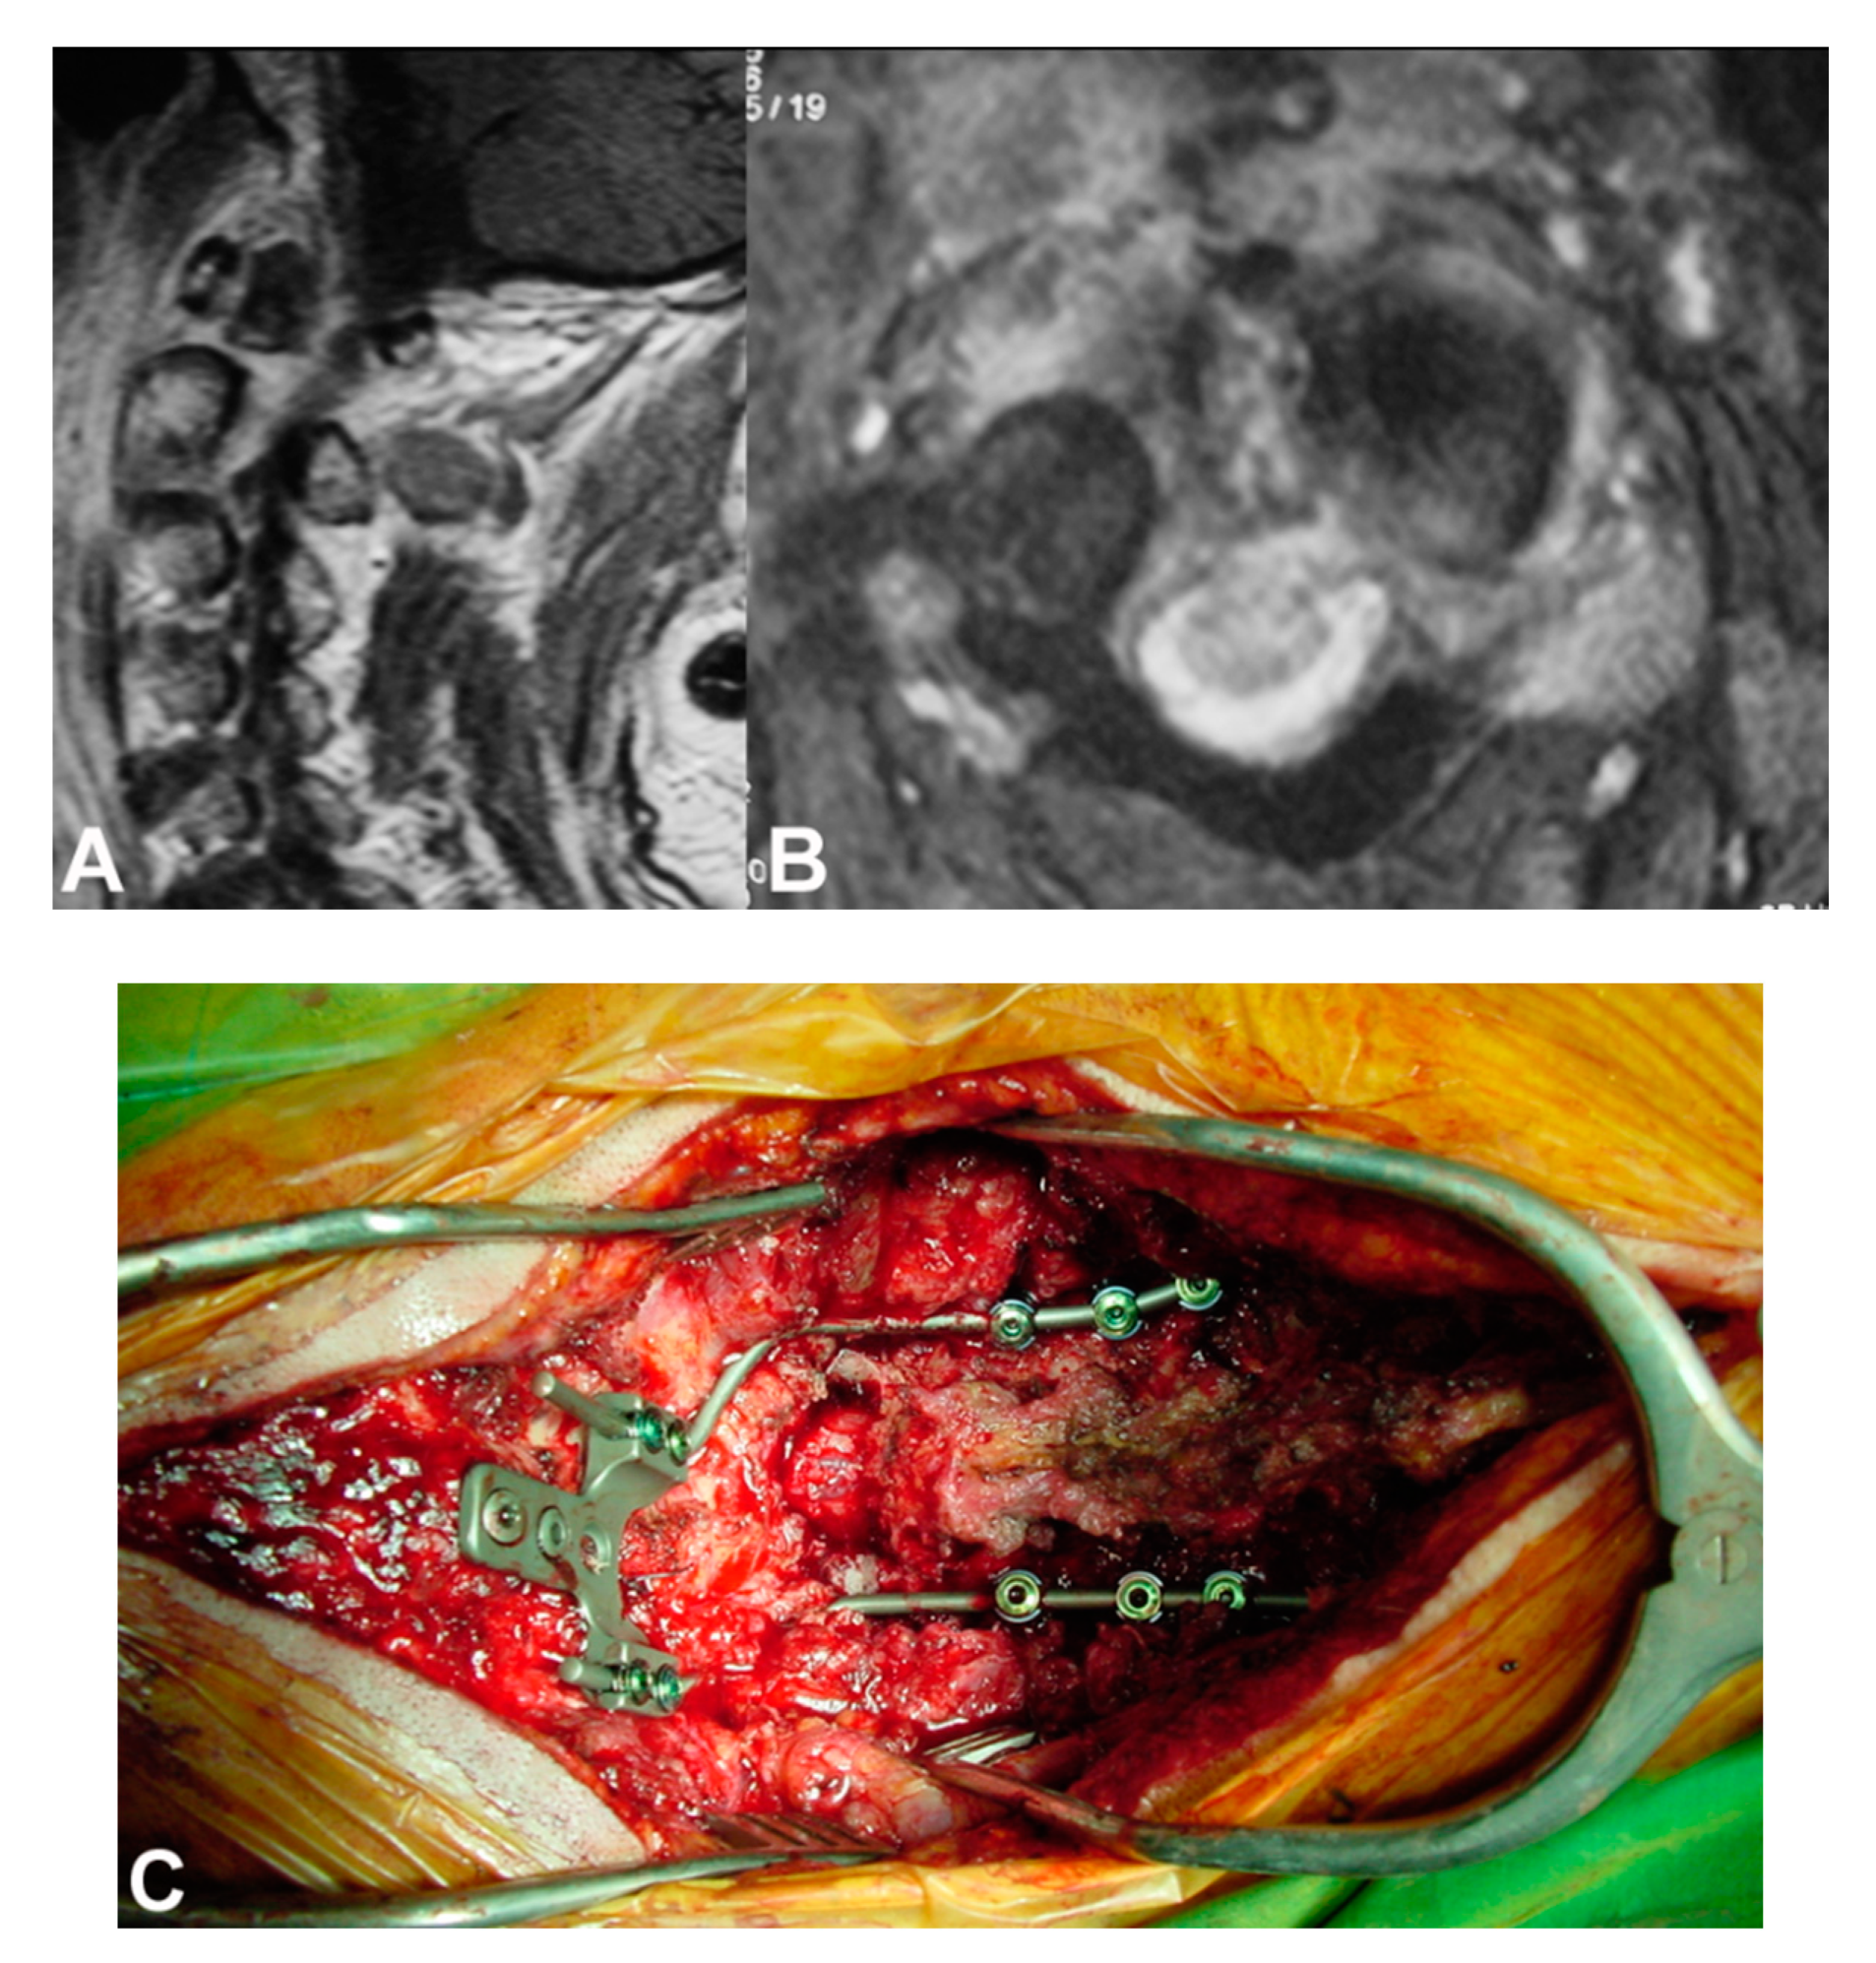

8. Conservative Treatment Antibiotics

9. Surgical Management

- Mavrogenis, A.F.; Igoumenou, V.; Tsiavos, K.; Megaloikonomos, P.; Panagopoulos, G.N.; Vottis, C.; Giannitsioti, E.; Papadopoulos, A.; Soultanis, K.C. When and how to operate on spondylodiscitis: A report of 13 patients. Eur. J. Orthop. Surg. Traumatol. 2016, 26, 31–40. [Google Scholar] [CrossRef] [PubMed]